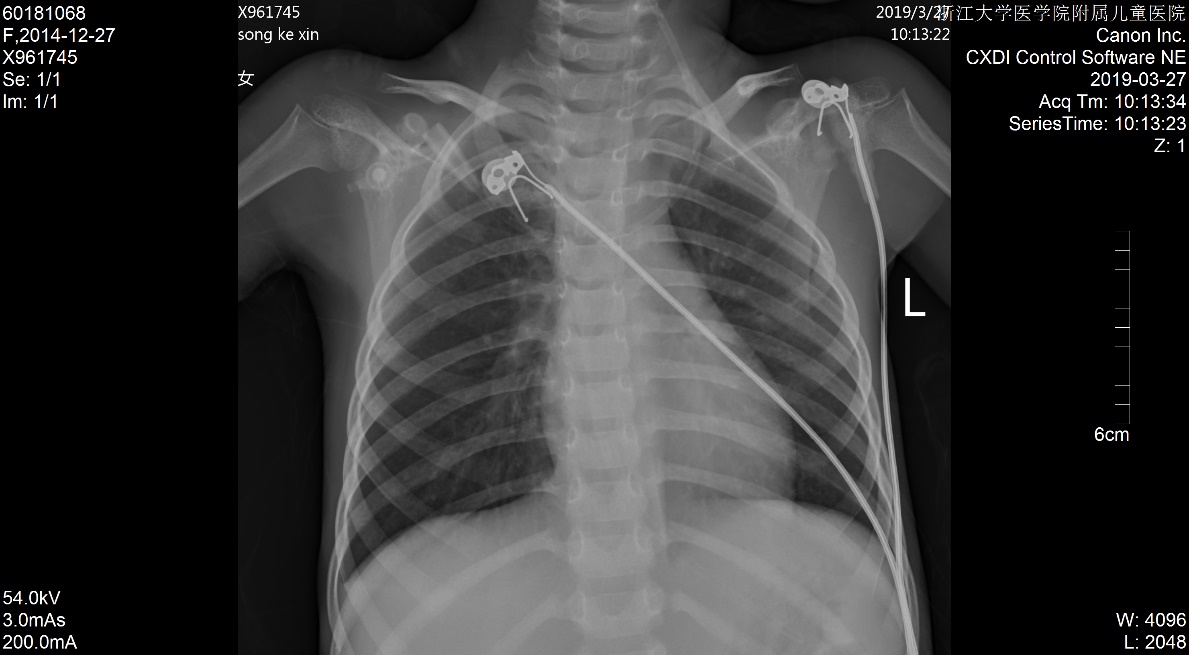

1 资料与方法患儿女,5岁2月,因“多尿、多饮、多食3个月余,意识不清1天余”由外院转入。3个月余前出现多尿、多饮、多食,家长未重视,未就诊。1 d前出现意识不清,并抽搐3次,急送当地医院就诊,当时查体情况具体不详,查血气电解质示pH 6.87,pCO225.9 mmHg,Na+ 125.4 mmol/L, Glu 17.1 mmol/L,Lac 1.1 mmol/L,HCO3- 4.6 mmol/L,ABE -28.1 mmol/L。考虑诊断“糖尿病、糖尿病酮症酸中毒、脑水肿?”收住当地医院。在当地医院住院期间,予大量补液[约3 L/24 h,大部分为晶体液,可能因为低血压,因住院期间曾使用多巴胺10 μg/(kg·min)维持],住院期间出现氧饱和度不能维持,遂予气管插管并机械辅助通气。因病情持续恶化,联系后转入本院PICU。既往史、个人史、出生史无殊。爷爷及外婆有糖尿病及高血压病。入院查体:T 37.8℃,脉搏:146次/min,呼吸:38次/min(为机械通气),血压98/77 mmHg(1 mmHg=0.133 kPa),无特殊面容及畸形,体质量:11 kg,气管插管带入,经皮血氧饱和度95%,镇静状态,双侧瞳孔等大等圆,直径2 mm,对光反射存在,颈软,余神经系统无明显阳性体征,面色苍白,消瘦貌,双肺呼吸音粗,可闻及湿啰音,腹软,肝脾肋下未及,皮肤弹性略差,肢端凉,毛细血管充盈时间5 s。入院后查白细胞计数8.52×109/ L-1,淋巴细胞15.4%,中性粒细胞82.0%,超敏C反应蛋白17.33 mg/L;血气分析:pH 6.996,pO2 91 mmHg, pCO2 43.5 mmHg,Na+ 126 mmol/L,Glu 21.0 mmol/L,Lac 2.9 mmol/ L,HCO3- 10.1 mmol/L,ABE -20.6 mmol/L;血氨63 μmol/ L;生化五类:总蛋白34.9 g/L,白蛋白26.5 g/L,丙氨酸氨基转移酶24 U/L,天门冬氨酸氨基转移酶96 U/L,肌酐147 μmol/L,尿素12.38 mmol/L,肌酸激酶1 680 U/L,肌酸激酶-MB活性166 U/L,甘油三酯6.05 mmol/L,胆固醇6.11 mmol/L,淀粉酶3 094.5 U/L;尿常规:尿酮体++,尿蛋白++,尿糖++++,尿隐血+++;糖化血红蛋白16.5%;血清C肽测定:0.116 nmol/L;糖尿病自身抗体阳性;脑脊液常规、生化及培养无殊;血尿培养阴性;胸片:两肺弥漫性病变,双侧胸腔积液,肺水肿待排(图 1);心超:左室收缩功能稍减低(EF 0.53),少量心包积液,二、三尖瓣轻度反流;腹部B超:肝大、腹腔积液。考虑诊断“急性呼吸窘迫综合征、急性肾功能损伤、1型糖尿病、糖尿病酮症酸中毒、脑水肿、多浆膜腔积液”,予呼吸机支持[HFO模式,FiO2:85%,f:5.8 HZ,ΔP:36 cmH2O(1 cmH2O=0.1 kPa),MAP:25 cmH2O, OI:23)、多巴胺及肾上腺素泵注维持血压、甘露醇降颅压、胰岛素注射降血糖及其他对症支持治疗,患儿入院第3天酮症酸中毒基本纠正,第6天改无创通气(CPAP,Flow:10 L/min,PEEP:4 cmH2O),入院第10天改大气吸入,复查胸片基本好转(图 2),住院期间未再抽搐,在停呼吸机机械通气镇静后意识好转,但较激惹、躁动,肾功能逐步恢复,住院28 d后出院,出院前患儿意识清,能完成日常对答,查头颅MRI提示脑萎缩改变,复查肺部影像学未出现遗留性病变,复查心超未见心包积液。现规律随访近一年,胰岛素治疗血糖控制尚可,未遗留明显神经系统、呼吸系统等后遗症。本研究经浙江大学医学院附属儿童医院伦理委员会批准(批准号:2020-IRB-078),并经患儿家属知情同意。

| 图 2 入院第10天胸片 |